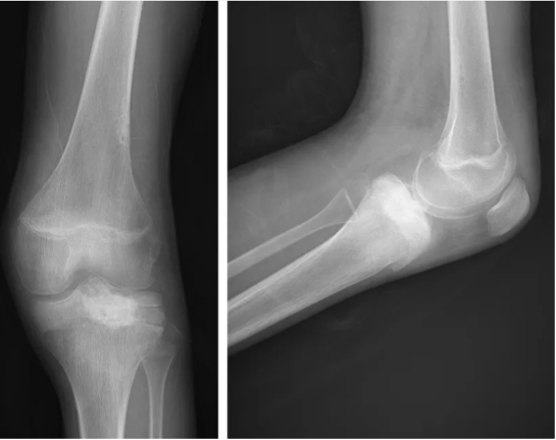

外院行经腘窝肿瘤刮除术,术后影像下显示:

X线片较术前未见明显改变,胫骨近端骨骺区不均匀透亮影,累及生长板。